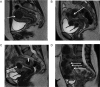

Uterine fibroids (also known as leiomyomas or myomas) are the most common form of benign uterine tumors. Clinical presentations include abnormal bleeding, pelvic masses, pelvic pain, infertility, bulk symptoms and obstetric complications.Almost a third of women with leiomyomas will request treatment due to symptoms. Current management strategies mainly involve surgical interventions, but the choice of treatment is guided by patient's age and desire to preserve fertility or avoid 'radical' surgery such as hysterectomy. The management of uterine fibroids also depends on the number, size and location of the fibroids. Other surgical and non-surgical approaches include myomectomy by hysteroscopy, myomectomy by laparotomy or laparoscopy, uterine artery embolization and interventions performed under radiologic or ultrasound guidance to induce thermal ablation of the uterine fibroids.There are only a few randomized trials comparing various therapies for fibroids. Further investigations are required as there is a lack of concrete evidence of effectiveness and areas of uncertainty surrounding correct management according to symptoms. The economic impact of uterine fibroid management is significant and it is imperative that new treatments be developed to provide alternatives to surgical intervention.There is growing evidence of the crucial role of progesterone pathways in the pathophysiology of uterine fibroids due to the use of selective progesterone receptor modulators (SPRMs) such as ulipristal acetate (UPA). The efficacy of long-term intermittent use of UPA was recently demonstrated by randomized controlled studies.The need for alternatives to surgical intervention is very real, especially for women seeking to preserve their fertility. These options now exist, with SPRMs which are proven to treat fibroid symptoms effectively. Gynecologists now have new tools in their armamentarium, opening up novel strategies for the management of uterine fibroids.